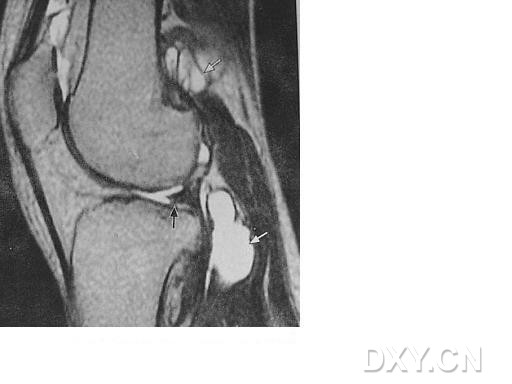

| 半月板纤毛化 外侧半月板后角内有横行的高信号影,类似半月板撕裂信号,腘窝囊肿